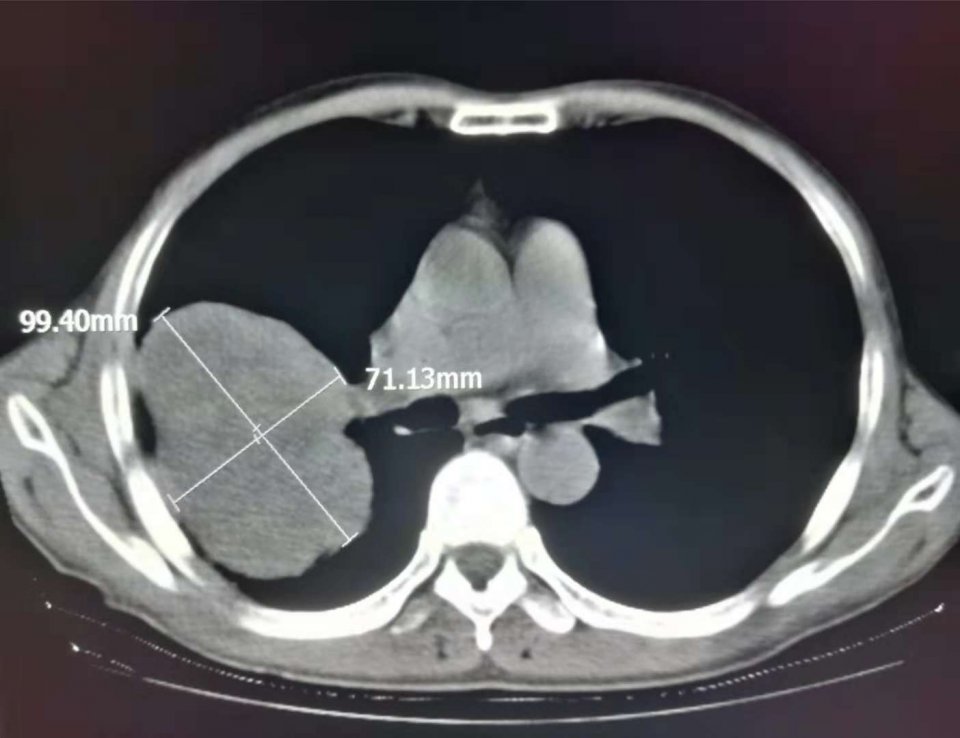

像这位老爷子,7厘米的大肺癌,跟肺门大血管粘连在一起,手术没有绝对把握,但是不手术,剩下多久的寿命恐怕就很难说。

手术做了3个多小时,术后做了化疗降低复发和转移风险。

一晃七年过去了,老人恢复得相当好: